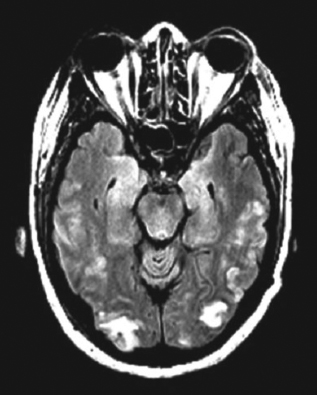

Her white blood cell count is 14,800/μL with a normal differential. Her red blood cell and platelet counts are normal. Serum chemistry, liver function, and coagulation test results are normal. Urinalysis reveals a protein level of higher than 500 mg/dL. A T2-flair image from an MRI scan is shown here.

PRES is a distinct radiologic pattern of vasogenic edema in the setting of neurotoxicity that is strongly associated with eclampsia. The syndrome is distinguished by its focal, symmetric distribution in watershed areas of the parietal and occipital areas of the brain. Contrary to the name, PRES can affect frontal, brainstem, or cerebellar zones as well. Symptoms associated with PRES include headaches, vision changes, focal neurologic signs, alterations in mental status, and seizures. PRES is not unique to eclampsia and is observed in a number of other conditions (Table). PRES is thought to be fully reversible with management of the underlying disorder.4,5